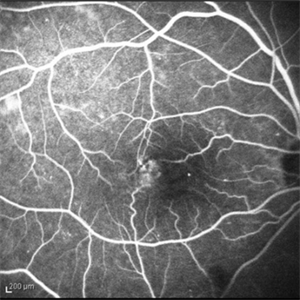

Idiopathic Juxtafoveal Telangiectasia, Type 2

Nov 6 2014 by Thomas A. Ciulla, MD, MBA, FASRS

Note the telangiectactic vessels just temporal to the FAZ.

Photographer: Thomas Steele

Condition/keywords: idiopathic macular telangiectasia, juxtafoveal telangiectasis, parafoveal telangiectasia